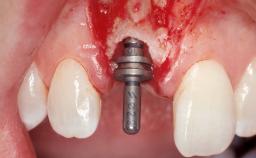

| # of Implants | 1 |

| Type of Implants | One-Piece |

| Attachment | One-Piece |

| Placement Protocol | Immediate implant placement |

| Bone Augmentation | Horizontal|Simultaneous |

| Augmentation Materials | Xenogenous|Membrane |

| Soft Tissue Grafting | Simultaneous |